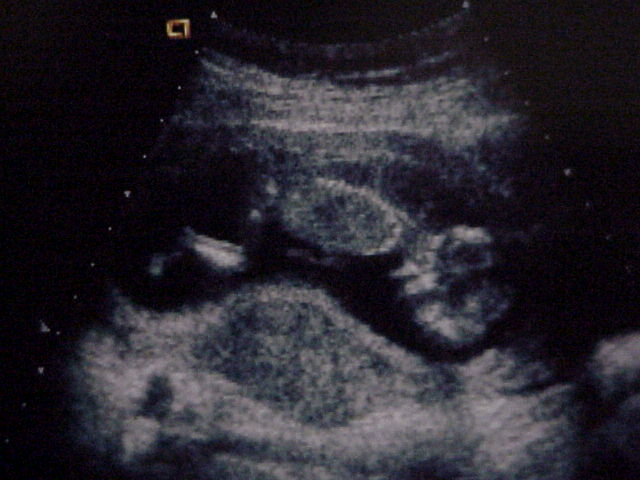

Close up of the baby.